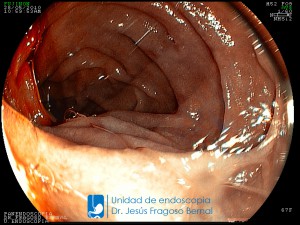

La Unidad de Endoscopía fue creada en 2002 por el Dr. Jesús Fragoso Bernal, es pionera en el estado por la utilización de la tecnología más avanzada, que nos permite ofrecer servicios integrales de diagnóstico y tratamiento para las enfermedades del aparato digestivo.

El profesionalismo de nuestro personal, altamente especializado, se distingue por la calidad y calidez de nuestros servicios con el objetivo de brindar una atención de excelencia en el ambiente más confortable para comodidad y seguridad de nuestros pacientes.

"La Unidad de Endoscopía se ha caracterizado por un progreso continuo desde su inicio marcando la pauta en los procedimientos endoscópicos en el estado de Tlaxcala y estando siempre a la vanguardia tecnológica."

Dr. Jesús Fragoso Bernal